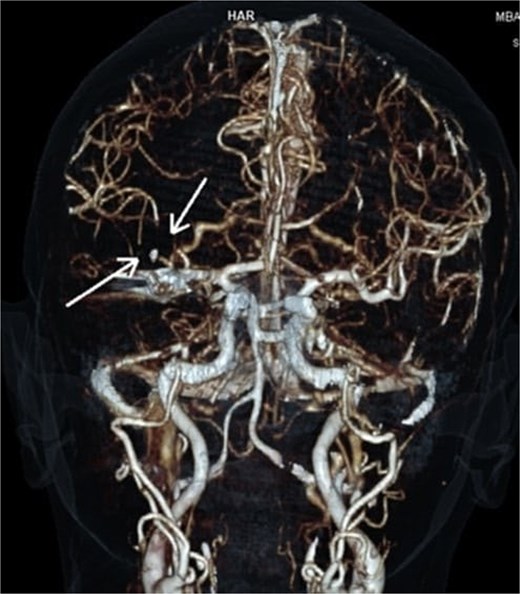

On arrival at the hospital emergency department, ~2 h after the GP visit, moderate-to-severe left hemiparesis, dysarthria, and altered mental status were observed. Neurological consultation and computed tomography (CT) angiography of the head revealed an AIS with proximal occlusion of the M2 segment of the right middle cerebral artery (Fig. 1). Thrombolysis with tenecteplase 0.25 mg/kg (3 ml) was performed. Within 1 h, significant clinical improvement was observed with almost complete recovery of motor function on the paralyzed side.

CTA reconstruction indicating proximal occlusion of M2 segmental branches of MCA (arrows).